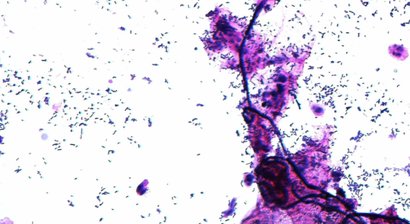

Betreuung von akuten Infektionen

Die häufigsten Ursachen für den Symptomkomplex Vaginitis sind verschiedene Hefepilze (Candida albicans, Candida glabrata, Candida krusei u.a.) und/oder verschiedene anaerobe Bakterien, die zusammen die sog. Bakterielle Vaginose (BV) verursachen.Die Symptome sind subjektiv und können s...